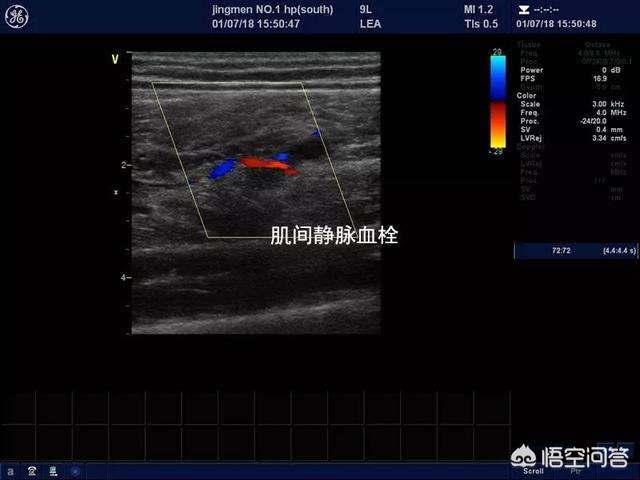

如果您发生这种情况的时候正处于住院期间,那么建议您一定与您的主治医生沟通,做一个下肢的血管彩超检查,明确是否存在下肢静脉血管的血栓形成或者是微小血栓形成。彩色超声检查针对诊断下肢静脉血栓形成特异性比较高,准确率也比较高,而且费用也不是特别贵,一般在100元左右。